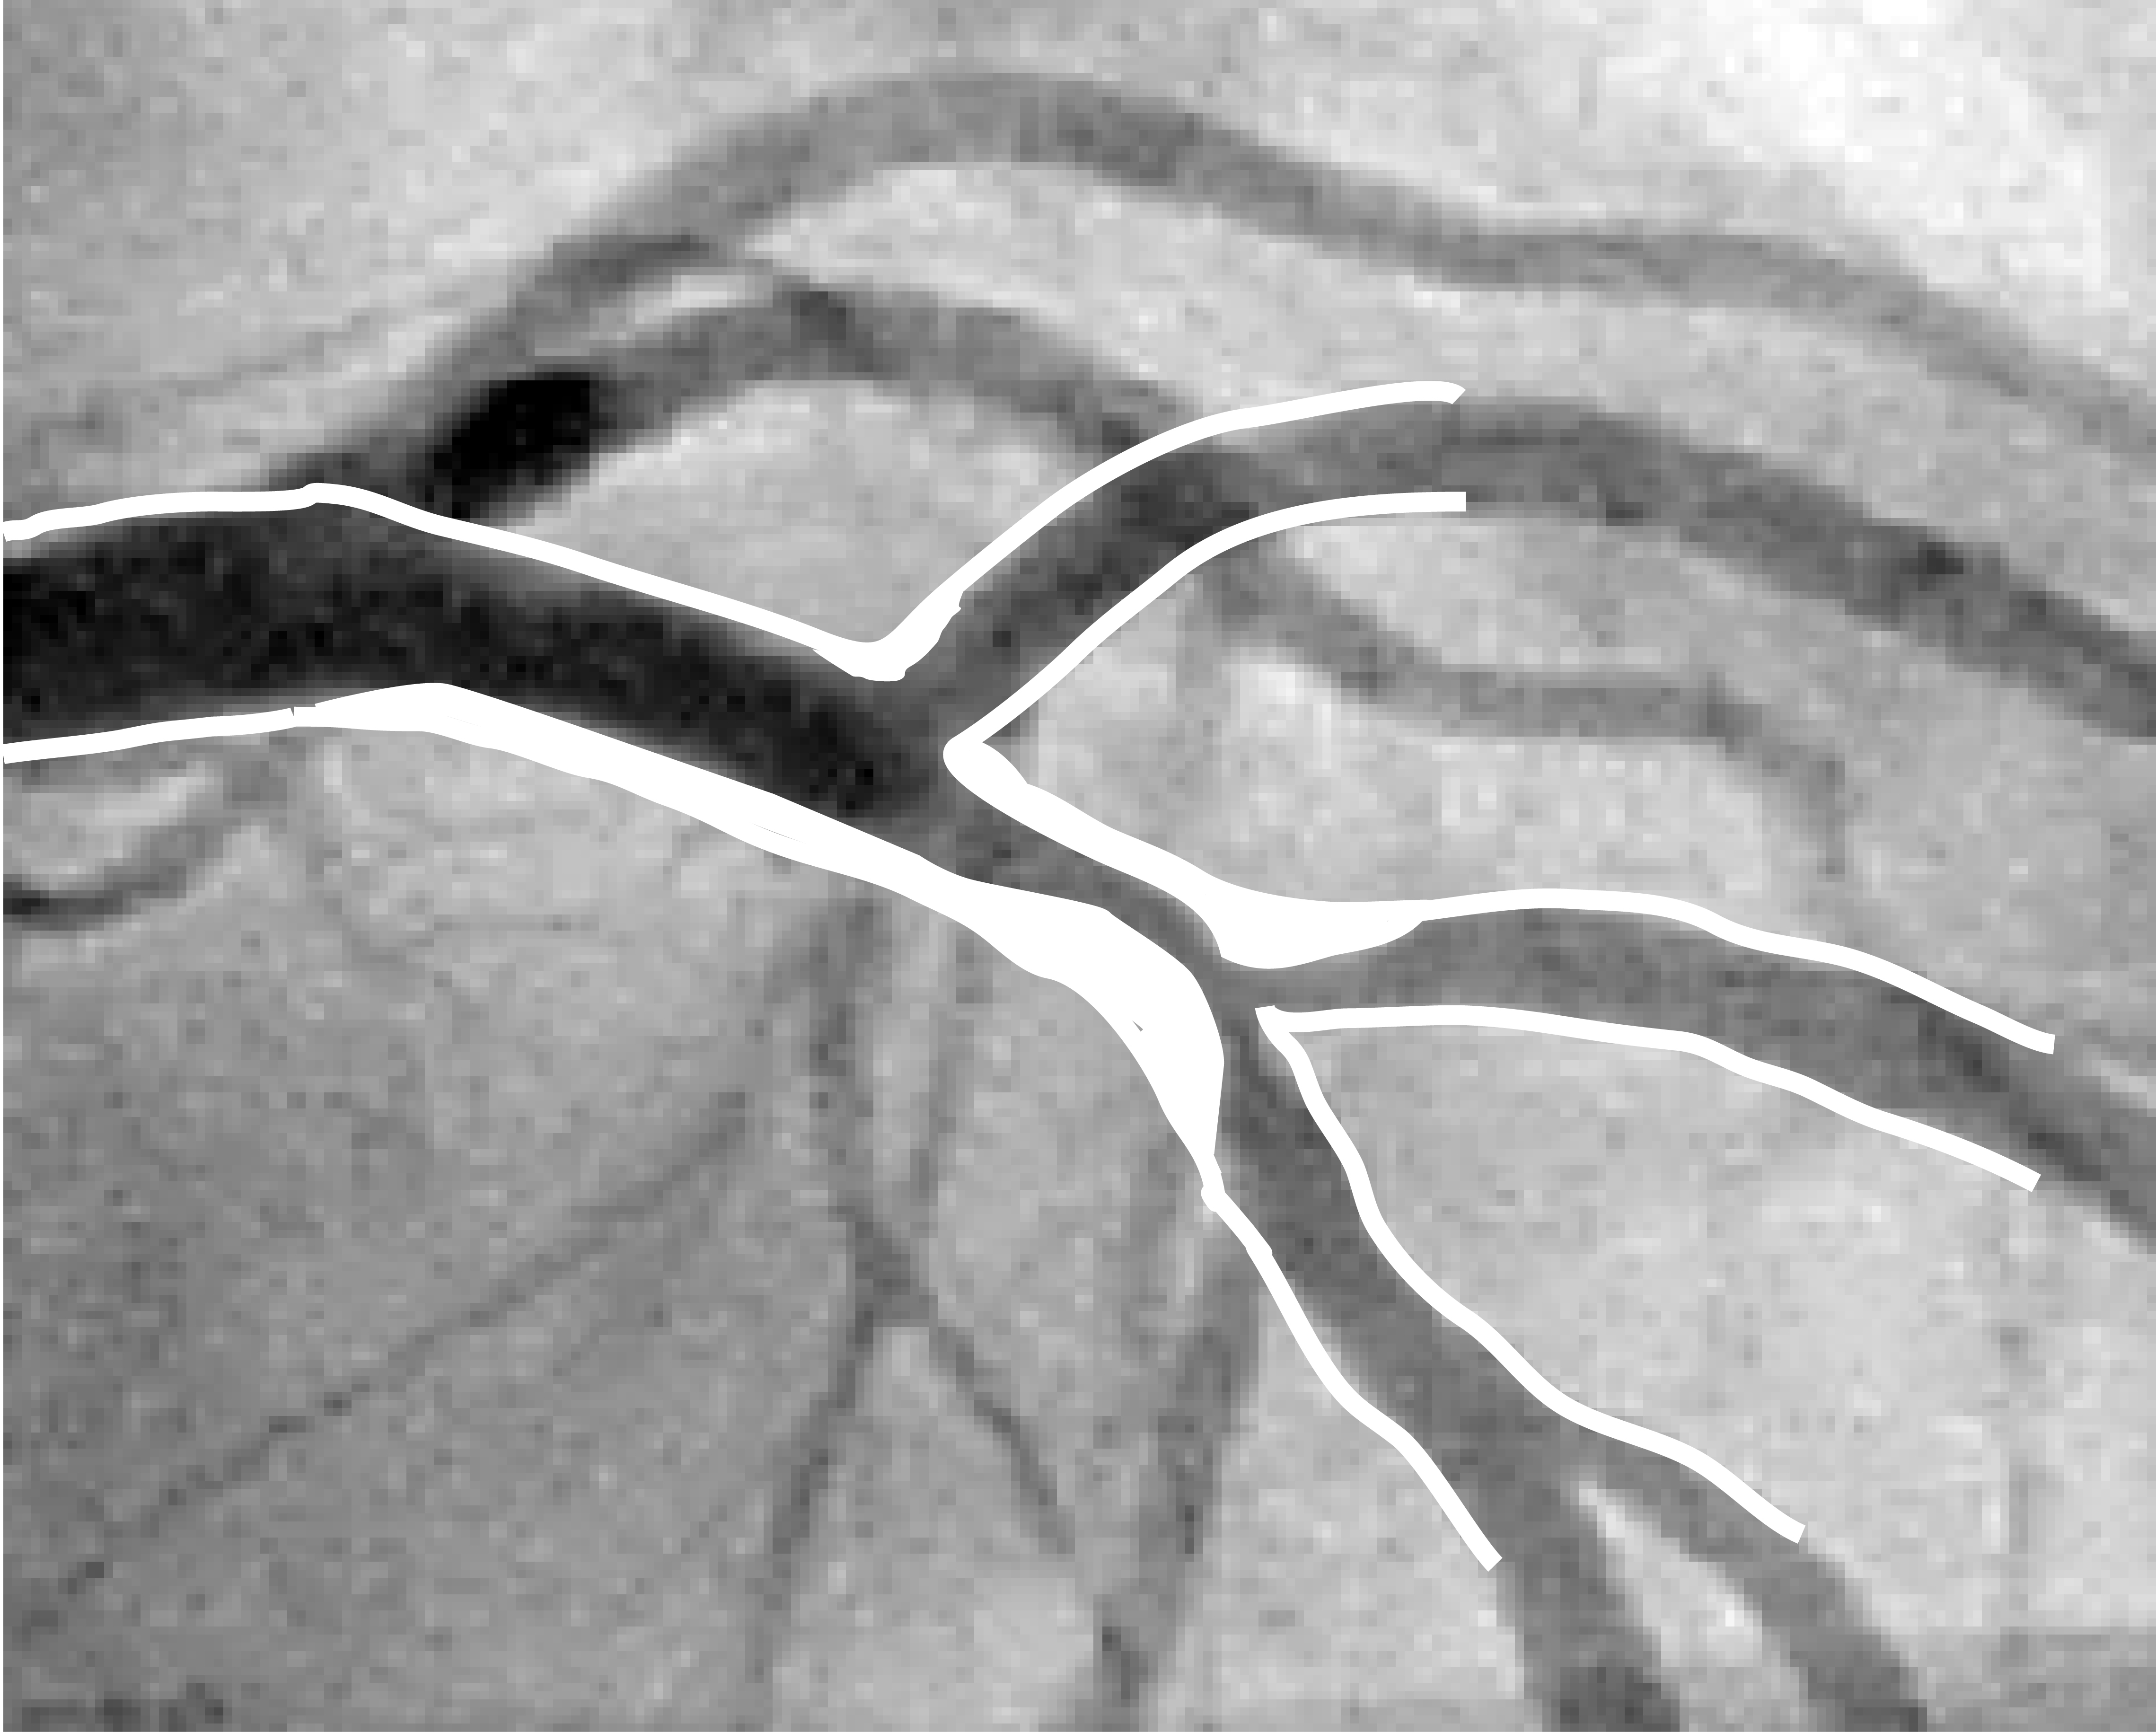

A novel framework for fluid/structure interaction in rapid subject-specific simulations of blood flow in coronary artery bifurcations

Abstract PDF FIG 1 Odgovor recenzentu A Rezime rada ID 2792 A NOVEL FRAMEWORK FOR FLUID/STRUCTURE INTERACTION IN RAPID SUBJECT-SPECIFIC SIMULATIONS OF BLOOD FLOW IN CORONARY ARTERY BIFURCATIONS Fig 2 Fig 3 Fig 4 Fig 5 Fig 6 Fig 7 Fig 8 Fig 9 Fig 10 -